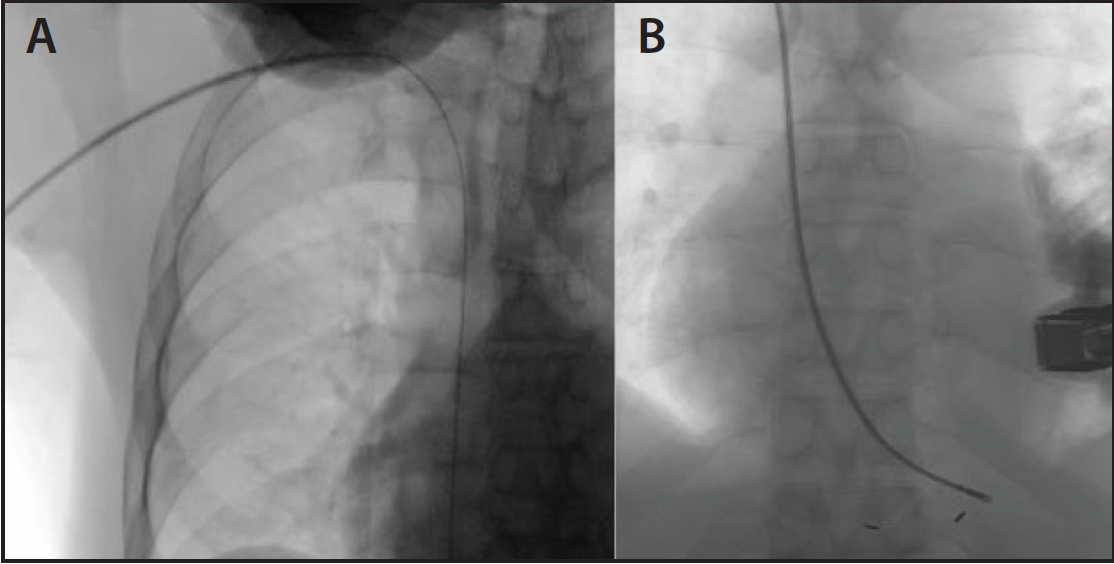

Figure 2. After completing a TAVR procedure, a 125-cm multipurpose catheter was inserted in the right iliac artery while a 14-F TF sheath was pulled back in the right external iliac artery (A). A 9-mm balloon was inflated in the right external iliac artery to tamponade the flow in the right external iliac artery while using the harvested sutures from the preclose technique (B).

In an example shown in Figure 2, a multipurpose catheter was inserted via RA into the right iliac artery. Subsequently, a 9-mm balloon was inflated in the external iliac artery while the 14-F sheath was removed and sutures were harvested from the preclose closure device and tied to achieve hemostasis without significant bleeding.